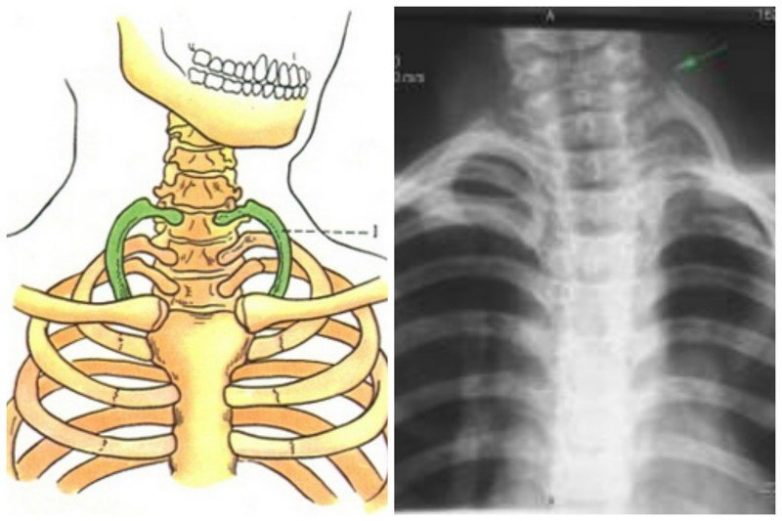

Шейное ребро

Лишь 1% (по мнению других ученых всего 0,5%) населения планеты имеют этот атавизм. Внешний облик человека, имеющего эти ребра, характерен — опущенные плечи и тюленеподобный вид. В период первичной сегментации мезенхимы у эмбрионов человека имеется 29 пар ребер. В дальнейшем развиваются только 12 грудных пар, а остальные подвергаются обратному развитию. Шейные ребра как аномалия развития формируются вследствие нарушения процессов редукции их зачатков.